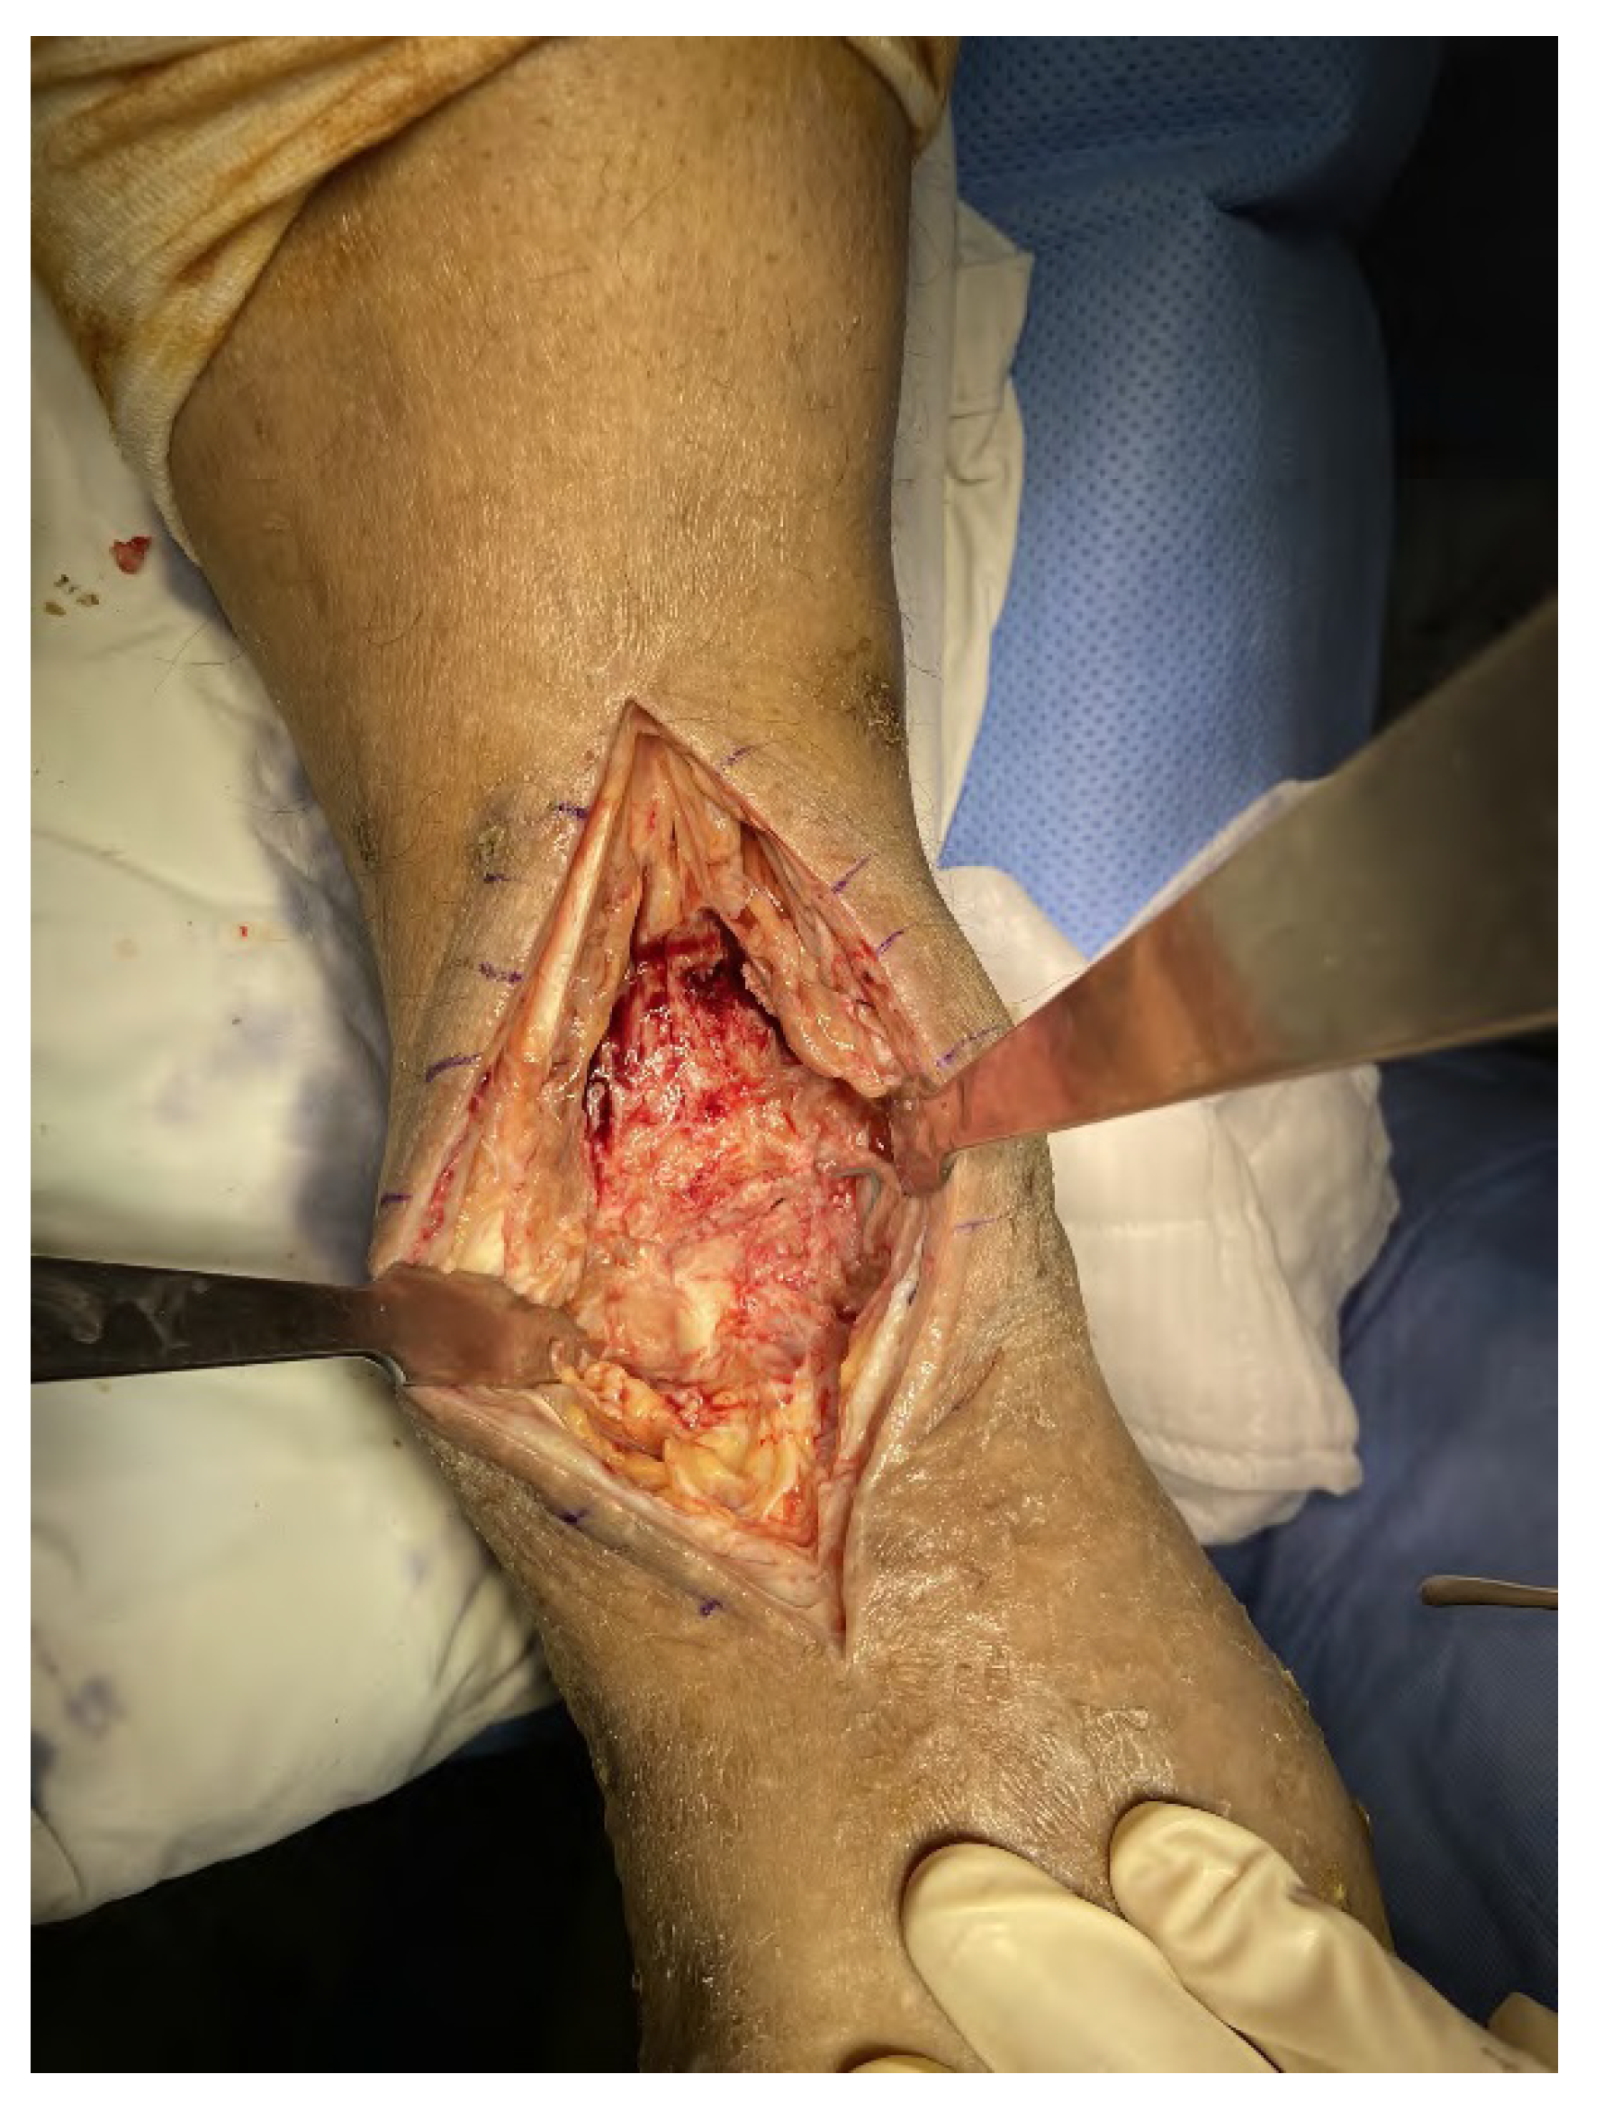

2.2. Surgical Procedure